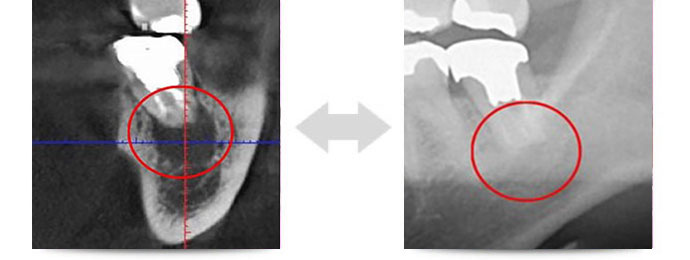

当院には通常の2次元レントゲンよりも、精度高く撮影できるCTを導入しています。これまで見えなかったものが見えるようになるため、治療精度や安全性、確実性が格段に向上します。

下の画像をご覧ください。

同じ部位を2次元と3次元で撮影したものです。赤丸のマークを付けたところが問題の起きている部分となりますが、2次元レントゲンではそれが確認できません。

確認できないということは「問題が起きていない」と判断されてしまいますので、そのまま放置され、気づいた時にはもう時すでに遅しということがあります。CT撮影を利用することで、このようなリスクを回避できます。